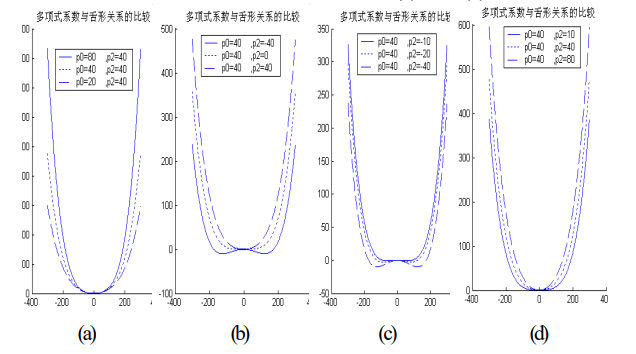

通过对舌体轮廓进行曲线拟合,可以用较少的参数表示舌体轮廓。对舌前部轮廓采用4次多项式拟合

发现曲线拟合参数与曲线形状的尖锐与圆钝有以下关系:

(1)由于舌体接近对称,因此奇次项系数一般相对较小,对舌体形状的影响较小,而常数项根本不影响曲线的形状。

(2)舌体的总体形状趋势取决于其最高项——四次项,在其他各项系数相同的情况下,四次项系数越大,曲线越尖锐;越小,曲线越圆钝。

(3)尖锐和圆钝的程度不但与四次项和二次项的符号关系有关,还与两个系数的绝对值关系有关。二次项与四次项系数绝对值之比越大,曲线的尖锐与圆钝越显著。